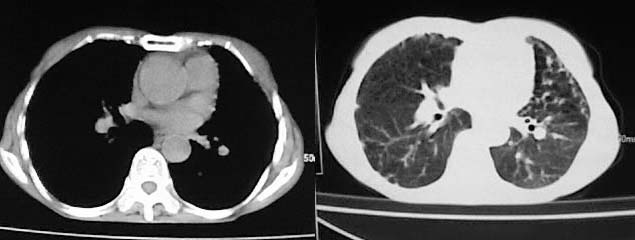

以下是引用有风的日子在2008-5-2 12:13:00的发言:[br][emb10][br][br]肺ca?有病理支持吗?[br][br]我看更象是肺tb并支扩、间质性肺炎。最好拿个病理结果来,不然这点影像资料诊断肺ca是难以服人的![br][br]至于主动脉瘤的诊断问题,国外认为≥4.0cm就可诊断了,国内对此诊断标准更为严格。患者升主动脉明显增粗,即>4cm。你诊断个升主动脉扩张并不为过!